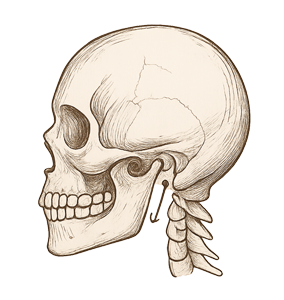

Çene eklemi (Temporomandibular Eklem – TME), alt çenenin kafatasına bağlandığı hareketli bir yapıdır.

Çene eklemi (Temporomandibular Eklem – TME), alt çenenin kafatasına bağlandığı hareketli bir yapıdır. Bu eklemde yaşanan fonksiyon bozuklukları; çene ağrısı, baş ağrısı, çiğneme güçlüğü, çene kilitlenmesi ve eklemden ses gelmesi gibi şikâyetlerle kendini gösterebilir. Genellikle stres, diş sıkma, kötü kapanış alışkanlıkları veya travmalar bu problemleri tetikler.

TME rahatsızlıklarının tedavisi, öncelikle detaylı bir teşhis ile başlar. Klinik muayene, çene hareket açıklığı değerlendirmesi ve gerekirse MR gibi ileri görüntüleme yöntemleriyle eklemin durumu analiz edilir. Tedavi; gece plağı kullanımı, egzersizler, ilaç tedavisi ve bazı durumlarda eklem içi enjeksiyonları içerebilir.

Kavi Diş Kliniği olarak, çene eklemi hastalıklarını hem fonksiyonel hem de multidisipliner yaklaşımla ele alıyor, hastalarımıza ağrısız ve sağlıklı bir yaşam sunmayı hedefliyoruz. Gerekli durumlarda fizik tedavi ve psikolojik destek gibi ek yönlendirmelerle süreci destekliyoruz. Kronikleşmeden müdahale edilen eklem sorunları, daha kısa sürede ve kalıcı olarak iyileştirilebilir.